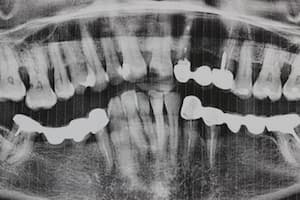

До

После

Удаление 7 зубов, установка 11 имплантов Straumann, временное и постоянное протезирование всех зубов с учетом формы, цвета и размера зубов. Работа с мягкими тканями. Импланты использовались для немедленной нагрузки.